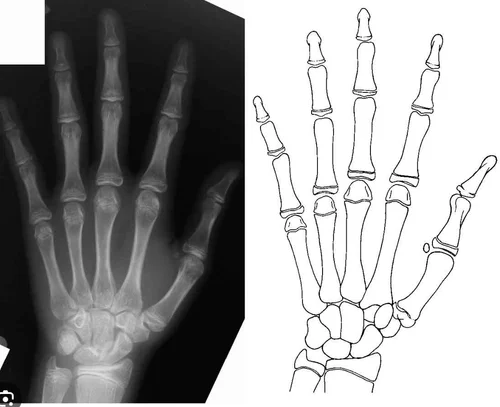

Relationship between hand and wrist bone age assessment methods - PMC

Figure 2 from Classification of hand-wrist maturity level based on ...

Digital radiographic evaluation of hand-wrist bone maturation and ...

Sanders's skeletal maturity staging system. (A) Stage 1 (juvenile slow ...